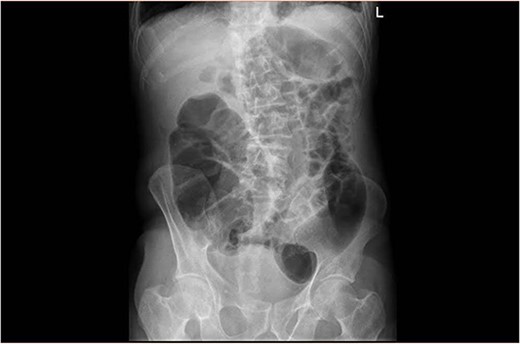

Upon clinical examination, the patient was vitally stable. Abdominal examination revealed a distended abdomen with generalized tenderness. Digital rectal examination revealed an empty rectum with no palpable masses. Laboratory investigations were unremarkable (Table 1). Abdominal X-ray was done (Fig. 2) and showed dilated large bowel loops suggestive of bowel obstruction. Enhanced CT scan of the abdomen and pelvis was obtained (Figs 3–5) and showed a dilated large bowel loop, with air fluid level. A 2.5-cm gallstone was noted, impacting the sigmoid colon and causing partial large bowel obstruction. There was evidence of pneumobilia with air foci within the gallbladder with a suspected fistula with the hepatic flexure.